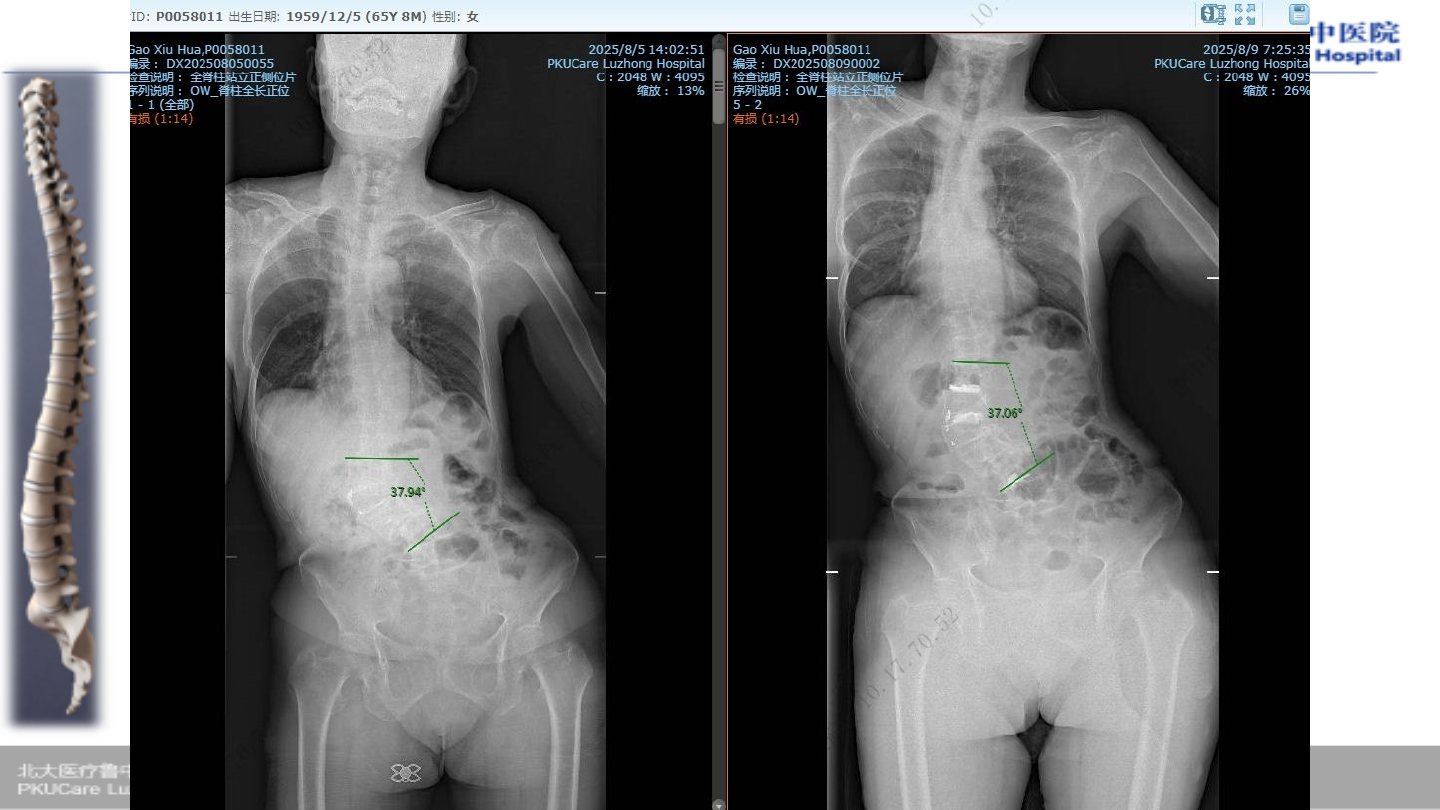

u

患者:高某,女性,

65

主诉:

腰疼伴行走困难,双下肢麻木

1

症状:腰部疼痛,双下肢行走困难,双下

肢小腿外侧疼痛麻木

.

Oswestry

功能障碍指数(

ODI

):

85%

VAS:8

病例

2

术前腰椎

X-ray